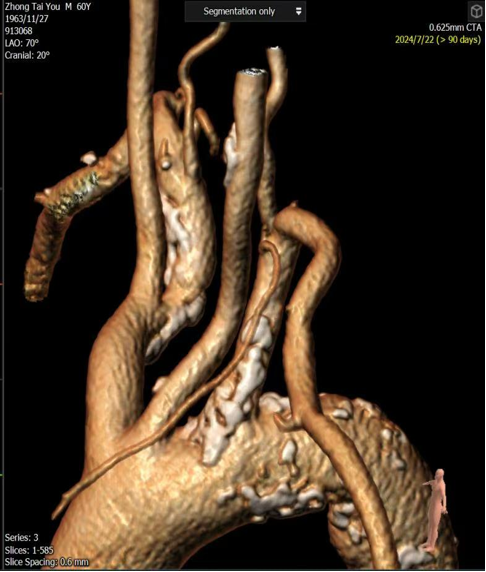

核心技术:CTA三维重建与投射角度模拟

本技术的核心在于利用CTA原始数据进行三维重建,在工作站上模拟术中造影机的各种投照角度(如左前斜LAO、右前斜RAO、加头位CRA、加足位CAU),从而在术前预先确定“最佳工作角度”。

右锁骨下动脉与颈动脉开口狭窄(对吻支架技术):

对于头臂干分叉处病变,需要同时对右锁骨下动脉和颈动脉植入支架(对吻支架)。术前CTA重建确定了最佳角度,术中直接采用该角度进行造影和支架释放,确保了双支架的精准定位,避免相互影响。

图:CTA图像

图:术中CTA图像指导导丝导管方向